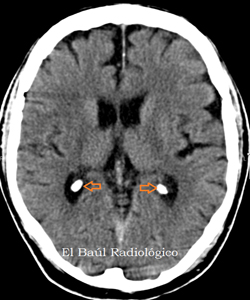

Plessi coroidei

- Focolai di Hamer: 2 e 23 del Tronco Cerebrale.

- Funzione: sono piccoli organi situati dentro il Sistema Nervoso Centrale, in particolare nel cervello, accanto ai ventricoli. Sono incaricati di formare il Liquido Cefalorachidiano (LCR) che serve da protezione al Sistema Nervoso Centrale. La maggior parte di questo liquido si forma in essi e si rinnova nell'uomo ad un ritmo di 6 o 7 volte al giorno.

- Senso della Attivazione (Conflitto): non poter ragionare correttamente per avere il cervello asciutto o perché non è sufficientemente idratato. Necessità di flusso del Liquido Cefalorachidiano.

- Fase Attiva: aumento della funzione, adenocarcinoma (ependimoma).

- Fase Pcl: caduta drastica della funzione, necrosi caseosa, incapsulamento o caverne.